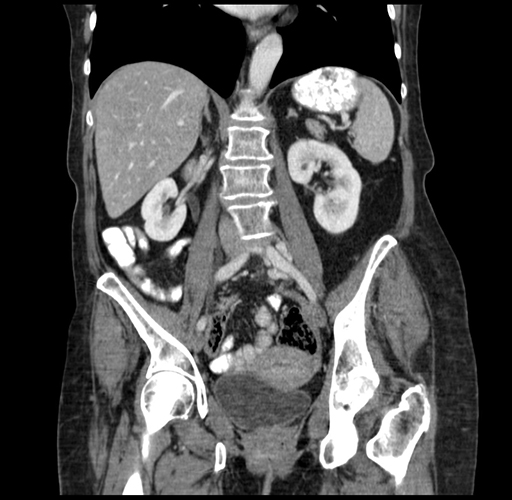

Pre-Chemo: Coronal Venous